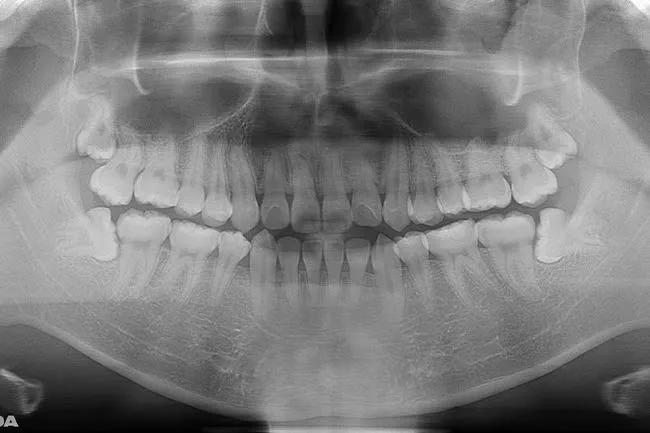

親知らずが横を向いて生えてきた口腔内

• 親知らずが斜めに生えてきた

• 手前の歯にぶつかって全然生えてこない

• 歯ぐきの腫れや痛みを繰り返している

親知らずが横・斜めに生えている場合は、歯ぐきの腫れや手前の歯がむし歯・歯周病になるリスクが高まります。トラブルを引き起こす前に、このような親知らずがあれば、早めに抜歯することをおすすめします。※ただし、服用中の薬によっては、主治医への確認が必要・服用を止めなければならない場合があるのでお早めに相談ください。